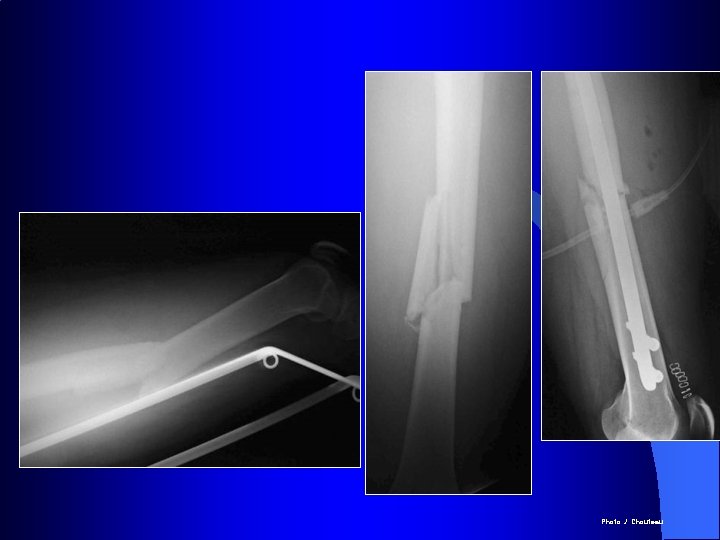

Photo J. Chouteau

Indication des plaques : les fractures métaphysaires

Classiquement l Principalement dans les fractures Diaphysaire

Le verrouillage est indiqué dans les fractures comminutives afin de préserver la longueur et empêcher la rotation

Le verrouillage est indiqué dans les fractures comminutives afin de préserver la longueur et empêcher la rotation Formation d’un gros cal grâce à l’hématome périfracturaire préservé